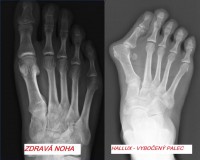

Aby ste vedeli,čo vybočený palec vlastne je, prikladám fotky haluxu, pre pochopenie, že sa nejedna o výrastok,ale len o vykĺbenú kosť.

PRE POROZUMENIE VIĎ FOTO

pre zväčšenie klikni na obrázok